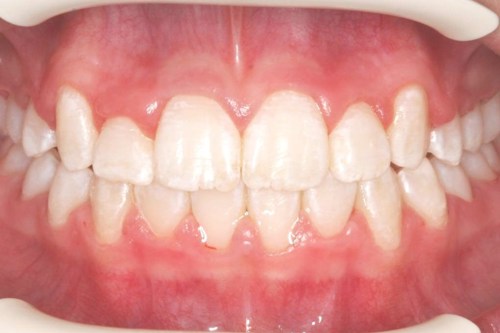

Nedenfor ser du et eksempel på en behandling, der kun har varet 16 måneder. Efter selve tandretningen, skal man regne med at gå med en holdebøjle i flere år, så tænderne ikke rykker tilbage på deres gamle skæve plads.

Billederne viser et tandsæt før tandretning og tandsættet efter 16 måneder med fast bøjle.